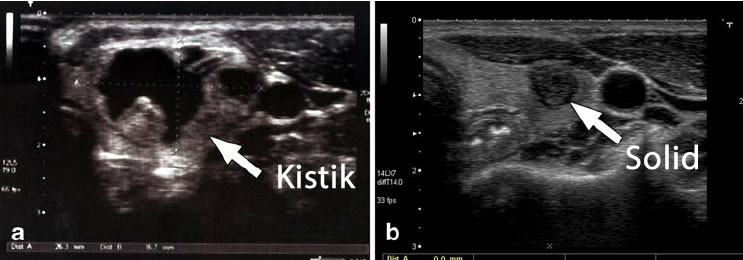

Tiroid nodüllerinde karşılaşılan “solid”, “kistik” ve “kolloid” terimleri, nodüllerin yapılarını ve içeriklerini tanımlamak için kullanılır. Bu terimler, nodüllerin ultrason ya da diğer görüntüleme teknikleriyle incelenmesi sırasında elde edilen bulgulara dayanır.

Solid Nodül: Bu, içerisinde sıvı olmayan, tamamen katı dokulardan oluşan nodüllerdir. Solid nodüller, iyi huylu (benign) olabileceği gibi kötü huylu da (malign) olabilirler. Bu yüzden detaylı inceleme ve takip gerektirirler.

Kistik Nodül: Kistik nodüllerin, içleri sıvı veya yarı katı şekilde olabilir. Büyük kısmı iyi huyludur, ancak tam olarak değerlendirmek için biyopsi gerekebilir. Kistik nodüllerin bazıları zamanla solidleşebilir ve bu durumda “karma” veya “mikst” nodül olarak adlandırılırlar .